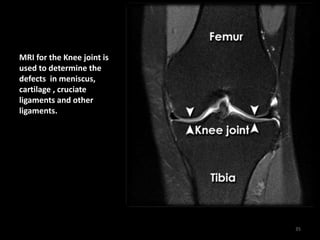

MRI – Knee – Normal

MRI for the Knee joint is

used to determine the

defects in meniscus,

cartilage , cruciate

ligaments and other

ligaments.